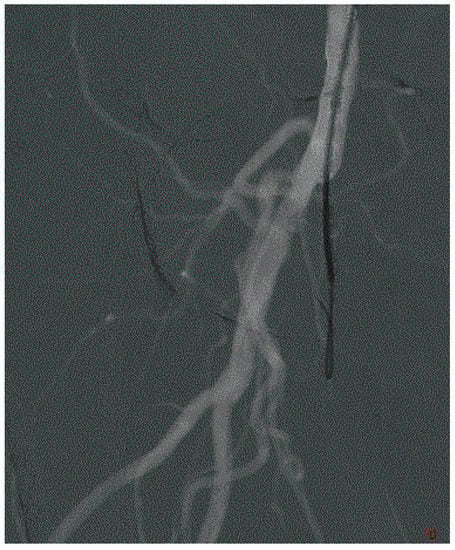

2. Define the Approach

3. Crossing the Lesion

4. Arterial Lesion Preparation